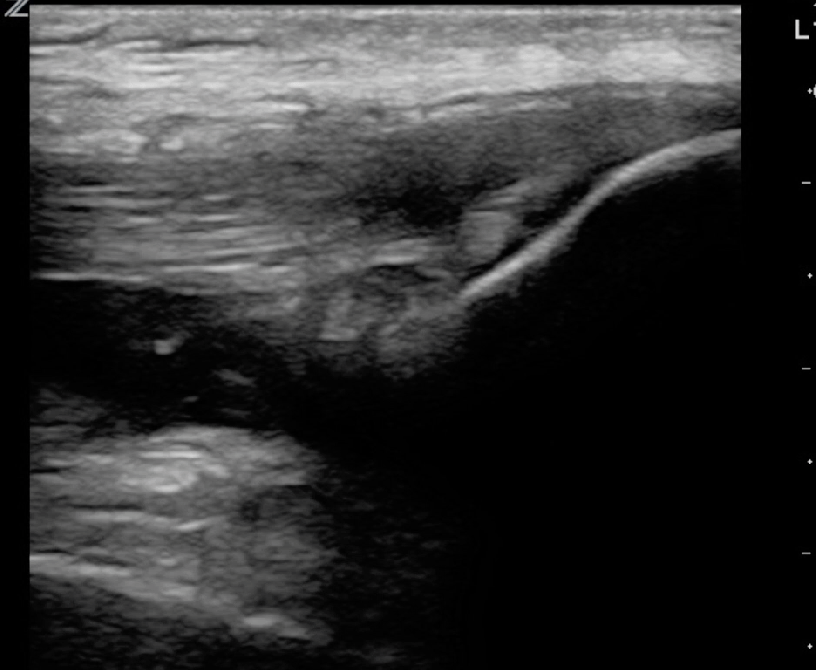

Sono of the Week – Quadriceps Muscle tear vs tendon rupture. Quick #Foamus #POCUS #meded

I wouldn’t say tendon rupture, maybe minor. More likely hemarthrosis and muscle tear. Thank you.

Absolutely correct! In the video you will find that was my conclusion as well. Thanks for the comment!